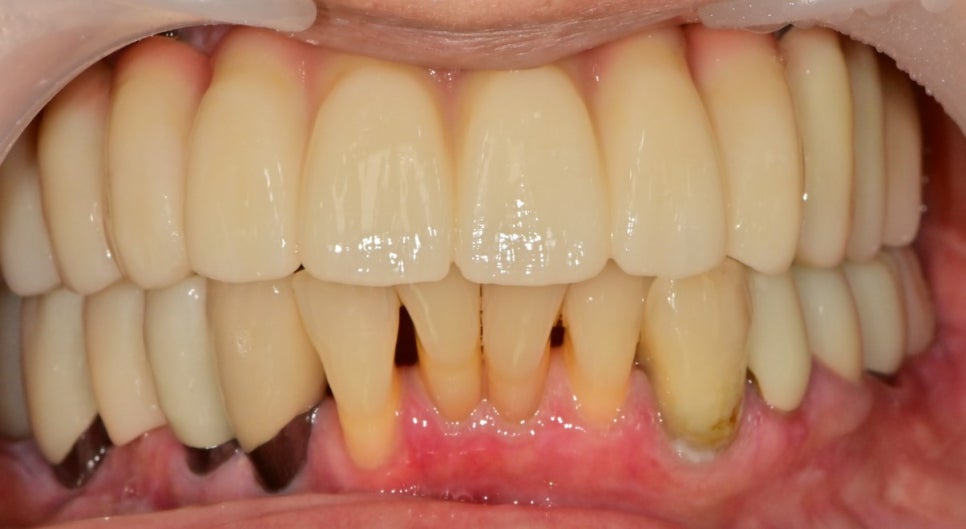

기능, 심미를 모두 만족할만하게 완성했습니다.

임플란트뿐 아니라 아래쪽 임플란트, 자연치아 주변도 염증관리가 잘되있습니다.

사진으로는 간략하게 소개가 되었지만

거의 10개월 가까이 시간이 소요되었습니다.

환자분께서도 치료기간중 너무너무 협조를 잘해주셔서

결과도 잘 나왔던 케이스가 아닌가 싶습니다.